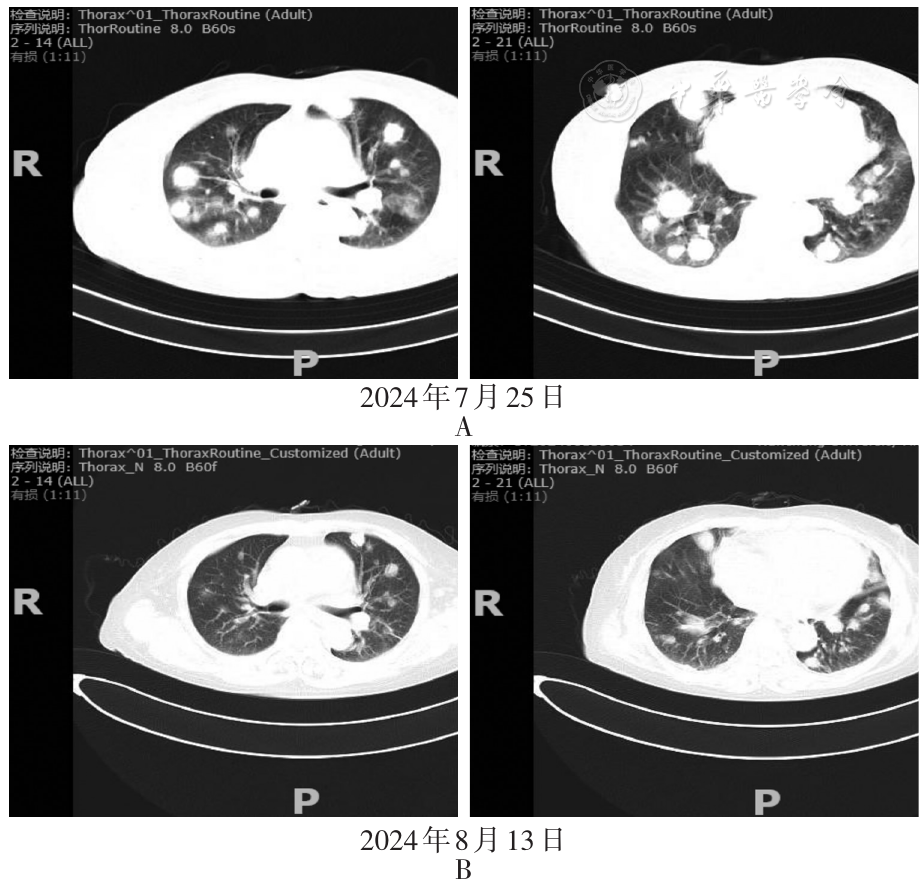

A 66-year-old female presented with fever, cough, and cutaneous nodular ecchymosis. The comprehensive examination revealed multiple nodules in both lungs, mediastinal lymphadenopathy, and splenomegaly; blood routine test: white blood cell count 2.15×109/L, hemoglobin 77 g/L, platelet count 67×109/L; C-reactive protein (CRP) 24.98 mg/L, erythrocyte sedimentation rate 35mm/1 h, ferritin>2 000.00μg/L, interleukin-2 receptor 7 500.00 U/ml, Epstein-Barr virus quantification positive, hepatitis B surface antigen, hepatitis B e antibody, and hepatitis B core antibody positive; bronchoalveolar lavage fluid next-generation sequencing(NGS) indicated Epstein-Barr virus positivity; bone marrow aspiration showed decreased platelet count and a bone marrow picture. Lung tissue biopsy immunohistochemistry (IHC) shows CD20(+ ) and Ki-67(+ ). Special stains: PAS (-) and PASM (-). In situ hybridization: EBER (+ ). The final pathological diagnosis suggests lymphomatoid granulomatosis cannot be excluded. The final diagnosis included HPS, PLG, EBV infection, chronic hepatitis B, and pulmonary infection. Initial treatment with anti-infectives, anti-inflammatory agents, and antivirals led to symptomatic improvement. However, the patient experienced recurrent pulmonary infections post-discharge. Ten months after onset, she was readmitted for fever and cough, and repeat lung biopsy confirmed B-cell lymphoma, prompting referral to hematology.